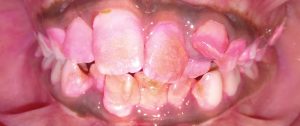

- Proposed a modification of Angle’s classification for application in primary dentition and various cross sectional studies have been carried out to validate its application.